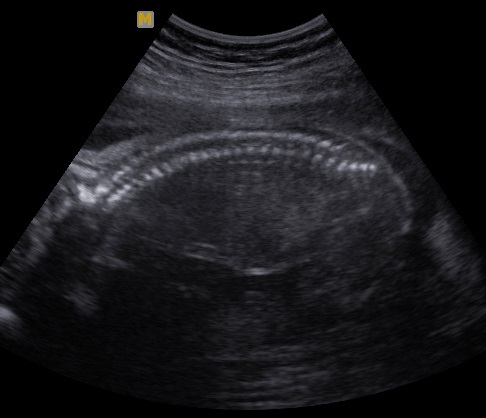

Columna vertebral

La columna vertebral, el eje neurológico que articula las funciones motrices y autonómicas del cuerpo comandadas por el cerebro y los sistemas vegetativos, es una estructura lineal mas sencilla de evaluar pero no menos importante desde el punto de vista diagnóstico por ser el asiento de las malformaciones más comunes del sistema, la espina bífida.